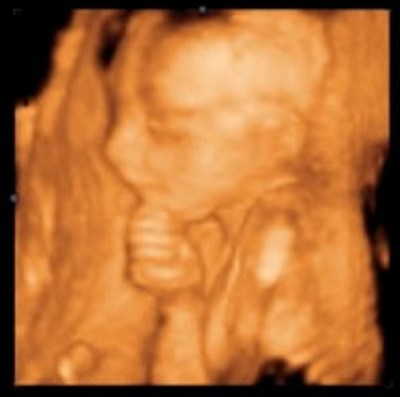

- The fetal heart begins to beat just 3 weeks and 1 day after fertilization.

- Brain activity can be measured by an EEG about 3 weeks later.

The ability of a fetus to survive outside the womb is currently defined as somewhere between 22 and 24 weeks.